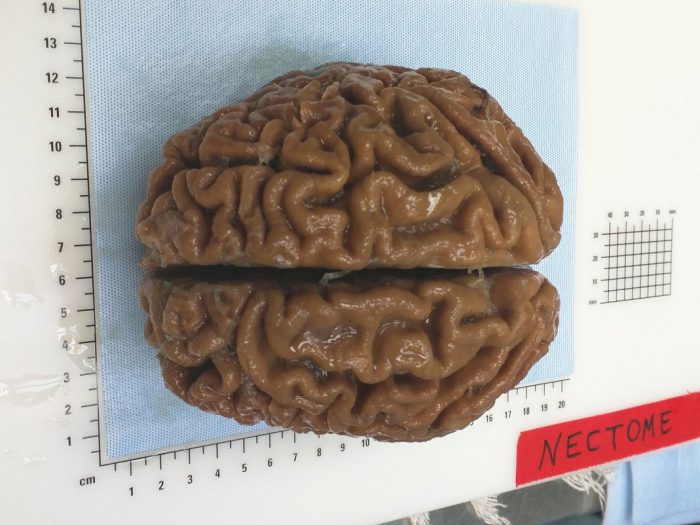

Μέχρι στιγμής έχουν γίνει επιτυχείς δοκιμές του πρώτου σταδίου, δηλαδή της κρυοσυντήρησης, στον εγκέφαλο ενός κουνελιού το 2016 και ενός χοίρου το 2018!

Εφόσον έχει γίνει η αρχική ταρίχευση θα αφαιρείται ο εγκέφαλος και θα μεταφέρεται στα εργαστήρια της Nectome όπου θα παγώνει στους -122 βαθμούς! Με αυτό τον τρόπο ο εγκέφαλος παγώνει, αλλά δεν μαζεύει κρυστάλλους, και θα μπορεί να διατηρηθεί για εκατοντάδες χρόνια με τους νευρώνες ανέπαφους, όπως έχουν δείξει τα πειράματα στα ζώα.

Η Nectome έχει λάβει μεγάλη ομοσπονδιακή χρηματοδότηση και συνεργάζεται με τον Έντουαρντ Μπόιντεν, νευροεπιστήμονα του ΜΙΤ, η τεχνική του οποίου για τη διατήρηση εγκεφάλου χοίρου κέρδισε πρόσφατα επιστημονικό έπαθλο ύψους 80.000 δολαρίων.